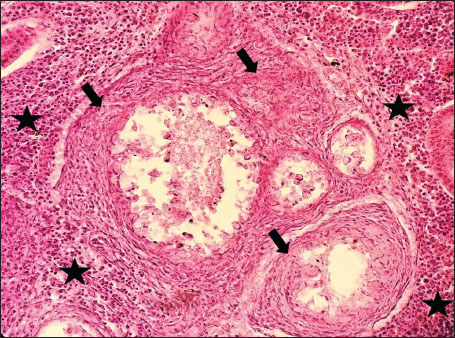

ABSTRACTBackground: The Mediterranean Sea has undergone significant ecological changes in recent decades, partly due to the introduction of non-native species. Lagocephalus sceleratus is an invasive Lessepsian species widely distributed in the Mediterranean, increasingly abundant along the Libyan coast, and potentially exposed to chronic environmental stressors. This species represents an important model for baseline pathological assessment in newly colonized marine environments. Aim: This study provides a descriptive histopathological assessment of kidney and gill tissues in adult L. sceleratus to document baseline tissue alterations without inferring direct environmental or pollution-related causation. Methods: A total of 150 adult specimens were collected from four Libyan coastal locations. Tissues were processed using standard histological techniques and evaluated semi-quantitatively (+, ++, +++) for lesion severity. Lesion severity grades were converted into ordinal numerical data and summarized using descriptive statistical approaches only. Results: Kidney tissues exhibited tubular degeneration, Bowman’s capsule dilatation, vascular congestion, extensive melanomacrophage centers (MMCs), and inflammatory lesions. Gill tissues showed disorganization of secondary lamellae, epithelial hyperplasia, edema, aneurysmal dilatations, vascular congestion, and MMC proliferation, some of which were associated with histologically observed parasitic structures. Conclusion: The observed alterations represent descriptive baseline tissue changes and should not be interpreted as direct evidence of pollution or specific environmental stressors. These findings provide reference data for future comparative pathological and ecological studies. Keywords: Lagocephalus sceleratus, Kidney, Gills, Histopathology, Melanomacrophage centers, Invasive species, Mediterranean Sea. IntroductionIn recent decades, the Mediterranean Sea has undergone profound ecological changes driven by the arrival and establishment of non-native marine species. Among these, Lagocephalus sceleratus has emerged as one of the most impactful Lessepsian migrants, due to its rapid geographic expansion, high ecological adaptability, and the presence of the potent neurotoxin tetrodotoxin in its tissues. This species has been widely documented to alter local fish communities, affect fisheries, and pose public health risks, making it an important target for biological and environmental assessment across the region (Katikou et al., 2022; Christidis et al., 2024). Fish are widely recognized as sensitive biological organisms in aquatic ecosystems, particularly in coastal habitats that are exposed to anthropogenic pressures such as industrial effluents, agricultural runoff, and untreated wastewater (Pinna et al., 2023). Among fish organs, the gills and kidneys are commonly regarded as sensitive to environmental stress, as they respond to physiological and pathological changes under environmentally suboptimal conditions. The gills, due to their large surface area and continuous exposure to surrounding water, are often the first tissues to exhibit structural alterations when fish encounter pollutants (Shahid et al., 2022). Histopathological changes in gills observed in polluted environments include epithelial lifting, lamellar fusion, hyperplasia, increased mucous cell density, and focal necrosis, which collectively reflect early physiological stress and potential compromise of respiratory function (Osman, 2010; Shahid et al., 2022). Similarly, the kidneys play crucial roles in osmoregulation, excretion of metabolic waste, and detoxification, making them highly vulnerable to chronic or systemic toxic effects (Wahidi et al., 2025). Documented renal lesions associated with chemical exposure include tubular deterioration, glomerular shrinkage, interstitial edema, and infiltration of inflammatory cells. These structural alterations often coincide with underlying biochemical disruptions, such as oxidative stress, impaired detoxification pathways, and activation of apoptotic mechanisms (Bernet et al., 1999; Authman, 2015). Despite the growing body of research on the ecological and toxicological implications of L. sceleratus, detailed histopathological assessments of this species remain scarce, especially in the southern Mediterranean basin, where environmental conditions and pollution profiles may differ from those in other regions. To date, detailed tissue-level studies of L. sceleratus from the southern Mediterranean are lacking, which limits the understanding of how this invasive species responds physiologically to local environmental stressors (Shakman et al., 2019; Ulman et al., 2021; Mohmmed et al., 2023). Accordingly, the present study aims to provide a comprehensive descriptive evaluation of histopathological changes in the kidneys and gills of L. sceleratus. The study is designed as a baseline histopathological assessment, focusing on tissue-level alterations without establishing causal links to environmental pollution or physicochemical stressors. By documenting structural aberrations and pathological features, this study contributes reference data for future monitoring and comparative studies in Mediterranean coastal ecosystems. Materials and MethodsSample designA total of 150 adult specimens of L. sceleratus, including both sexes, were collected from four Libyan coastal locations: Talamitha (n=39), Susah (n=34), Ain El-Ghazala (n=30), and Khalij Al-Bambah (n=47). Fish ranged in total length from 51 to 66 cm and in weight from 1.5 to 3.5 kg. Only apparently healthy adults were included, while juveniles were excluded to avoid age-related histopathological variation. Sampling was conducted opportunistically with assistance from local fishermen. All specimens were collected within a comparable seasonal window to minimize seasonal histopathological variability. Sex was recorded when possible; however, sex-based histopathological comparisons were not performed, as this was beyond the descriptive scope of the study. Fish were transported on ice at +4°C and examined in the Pathology Laboratory, Faculty of Veterinary Medicine, Omar Al-Mukhtar University (Mohmmed et al., 2023). Specimens were collected from a range of depths (0.5–70 m), with the majority from shallow waters (<10 m) and a subset (approximately 50 fish) from deeper locations (>30 m). Environmental physicochemical parameters such as temperature, salinity, and dissolved oxygen were not measured; therefore, no direct associations between histopathological findings and environmental variables were assessed. Tissue processing and histopathological examinationTissue specimens were fixed in 10% neutral buffered formalin for 24 hours. Following fixation, the samples were transferred to 70% ethanol for storage at room temperature. Subsequently, the tissues were processed for routine histopathological examination following standard procedures (Paul and Chanda, 2017). Paraffin embedding was performed, and 5 µm-thick sections were prepared using a microtome. Sections were stained with hematoxylin and eosin (H&E) and examined under a light microscope. Photomicrographs of representative lesions were captured using a high-resolution digital camera. Histopathological alterations were evaluated using a semi-quantitative scoring system adapted from Hose et al. (1996), Moshaie-Nezhad et al. (2021), and Alshailabi et al. (2023), where lesion severity was graded as mild (+), moderate (++), or severe (+++). Lesion severity grades (+, ++, +++) were converted into ordinal numerical values (1–3) for descriptive summarization of lesion severity. Due to the descriptive baseline nature of the study and the absence of a reference control group, inferential statistical comparisons were not emphasized or applied. Lesion severity scores were therefore summarized descriptively to avoid overinterpretation of the findings. Scoring was performed independently by two experienced observers, and representative lesions were confirmed across three sections per organ to ensure consistency. Tissues with visible parasitic structures were described separately from non-parasitized tissues to avoid conflating parasite-associated lesions with non-specific tissue alterations. The functional implications of the observed lesions were interpreted in accordance with Flores-Lopes and Thomaz (2011). Ethical approvalAll animal experiments conducted in this study were approved by the Ministry of Higher Education & Scientific Research and the Libyan National Committee for Biosafety & Bioethics, Libya. All procedures were performed in accordance with the relevant ethical guidelines, with session number 21/CH/25, dated 26/05/2021. ResultsHistopathological examination of the kidneyHistopathological examination of the kidney tissues of L. sceleratus revealed multiple alterations. Prominent melanomacrophage centers (MMCs), necrotic areas, dilatation of Bowman’s capsules, and vacuolar degeneration were observed (Fig. 1), associated with interstitial lymphohematopoietic tissue (Fig. 2). Dilated and congested blood vessels and extensive MMCs were also noted (Fig. 3). Renal degeneration surrounding lymphohematopoietic tissue, large clusters of MMCs, and thickened, congested vessel walls within fibrotic areas were evident (Fig. 4). Atrophic renal degeneration with necrotic and vacuolar changes was observed (Fig. 5). Severe inflammatory infiltration of lymphatic cells and granulomas with necrotic centers, surrounded by fibrous tissue, was detected (Figs. 6–7).

Fig. 4. Histopathology of the kidney in an adult L. sceleratus showing renal degeneration surrounding lymphohematopoietic tissue (stars), large MMC clusters (head arrows), and congested, dilated, thickened vessel walls within fibrotic areas (thin arrows). ×400 H&E.

Fig. 5. Histopathology of the kidney in an adult L. sceleratus showing atrophic renal degeneration (thick arrows), necrotic tissue (stars), and vacuolar degeneration (thin arrow). ×400 H&E.

Fig. 6. Histopathology of the kidney in an adult L. sceleratus showing atrophic renal degeneration with severe inflammatory infiltration of lymphatic cells (stars) and granulomas with necrotic content, surrounded by fibrous tissue (thick arrows). ×400 H&E.

Fig. 7. Histopathology of the kidney in an adult L. sceleratus showed the atrophic renal degeneration (stars), dilatation of Bowman’s capsules (thick arrows), and a granuloma (head arrow). ×400 H&E. Histopathological examination of the gillsThe gill sections of adult L. sceleratus exhibited multiple structural alterations. Secondary lamellae showed marked disorganization, while gill filaments displayed club-shaped deformities and occasional aneurysmal dilatations (Fig. 8). Vascular congestion with telangiectatic changes and proliferation of MMCs were also observed (Figs. 9–10). Edematous changes in primary lamellae, separation of the epithelial layer, lamellar aneurysms, and epithelial hyperplasia were documented (Figs. 10–11). Focal damage to secondary lamellae, disruption of lamellar architecture, presence of lamellar aneurysms, and unidentified parasitic structures were observed (Fig. 12). Pronounced vascular congestion and dilatation of lamellae due to red blood cell accumulation were noted (Fig. 13).